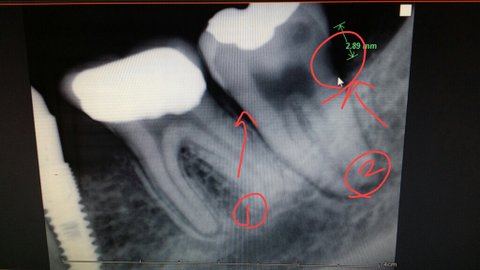

대학교 입학하면서 이제껏 미뤄왔던 교정을 시작했습니다. (현재 저에게 차트가 없고, 충치치료 등 오랜 치과통원으로 시기가 정확하지 않습니다만 이 맘때입니다.)      치아상태가 굉장히 안좋은데 여기에 길게 쓰기는 좀 그렇구요..  임플란트도 병행해야 하는 상태여서 임플란트 전문의와 교정전문의가 같이 있는 집에서 굉장히 가까운 치과에서 치료를 받았습니다.  걸어서 10분 거리였기 때문에 통원의 문제는 없었습니다. 당시에는...  (현재 임플란트6개고 앞쪽을 제외하면 모든 어금니가 충치떄문에 썩었어요. 하악발달이 덜 되서 기형치구요.)        처음에 교정잡을때는 1년~1년반 이렇게 의사선생님께서 말씀하셨는데 워낙 주변에서 교정기간이 점점 늘어난다는 얘기는 들었기 때문에  더 길게 할 것 감안하고 교정을 시작했습니다.      짧게 끝날 줄 알았던 교정은 예상을 넘어 결국 3년 반 정도 걸렸습니다. 그 사이 저는 새내기에 헌내기로, 헌내기에서 쓰레기로, 결국 1학기 남겨놓은 휴학생이 되어 있었습니다. 하지만 닥달하지는 않았습니다. 월정료(월마다 검진시 내는 비용)는 15개월까지만 내기로 했거든요. 교정이 길어진다고 해서 치과에서 이득볼 것 도 없다고 생각했습니다. 치아를 예쁘게 만들어주시는데 오랫동안 공써주시는구나... 그때는 그저 이렇게 감사히만 생각했습니다.     (지난주 화요일)  대학생활을 거의 내내 함께 한 교정장치를 드디어 빼는 날, 비보가 들려왔습니다. 충치가 생겼다고 합니다. 사실 어느 정도는 예상했었습니다. 치아가 워낙 약하고 교정을 하면 충치가 더 잘생긴다고 이미 얘기를 들었기 때문입니다. 그런데 왜 비보라고 말하냐 물으신다면 하루 세 번 양치하고 치간치솔, 치실, 리스테린까지 꼬박꼬박 정말 열심히 했습니다. 부모도 못알아보는 개가 되도록 술을 퍼억어도 양치만은 꼭 하고 잤습니다.      오른쪽 위와 왼쪽 아래. 두 군데가 안좋다고 합니다. 다음에 내원해서 치료를 하자고 하더라구요.(간호사?분께서 말씀해주심.) 간호사분(정확한 명칭을 몰라서 간호사로 통일하겠습니다.)께서 자그맣고 동그란 거울로 비춰보여주시면서 '까만 점 보이시죠. 이게 충치에요' 라고 가볍게 말씀하셨기에 저도 가볍게 생각하고 충치치료는 가까운 병원에서 받겠다고 말씀드렸습니다. 초반에 집에서 가깝다고 했는데 중간에 치과가 좀 먼 곳으로 이전했습니다. 왕복 두시간이 넘는 거리였기 때문에 시험을 준비하는 학생입장으로써 자주 가기가 힘들었습니다. 교정시작하면 선생님을 중간에 바꾸기가 어려워서 선생님따라 멀리있는 치과를 다니는 상황입니다. 그러시라고 답변을 들었구요.(간호사분께서)     (지난주 토요일)    다음주에 투명한유지장치(교정끝나면 의무적으로 해야 하는 기구입니다.)를 받으러 가야 했기 때문에 그때 같이 충치치료를 받고 싶다고 전화로 예약변경을 했습니다. 원래 약속잡던 오전시간에는 환자가 많아서 힘들다고 얘기를 들었습니다. 그래서 시간을 변경해서 그때 까지 충치치료를 받기로 했습니다.     (월요일) 투명한유지장치만 받았는데 다음달에 오시라고 합니다. 충치치료도 같이 받기로 했다니깐 예약시간변경이 안되있었습니다. 그래서 그 날 시간도 좀 기다렸던 것이었습니다. 화가 났지만 일처리하다보면 누락되는 부분도 있다고 생각해서 '그럼 전에 말씀드렸던 것처럼 충치치료는 집 앞에서 하겠다'고 했습니다. '알겠다'는 답변을 받았습니다.     (화요일)    다음날 아파트 상가에 있는 작은 치과를 갔습니다. 상황을 말씀드리니 충치도 사진을 찍어야 한다고 하더라구요. 오른쪽 위에는 이가 삭았는데 이 정도는 치료를 안해도 괜찮을 것 같다고 말씀하셔서 왼쪽 아래 (37번치아)만 사진을 찍었습니다.  (참고로 치과에서는 이가 삭은것과 충치 먹은 것을 같다고 표현한다고 합니다.  후에 치과에서 들은 얘기) 사진을 찍고 설명을 들으니 생각보다 상태가 심각했습니다. 치아와 치아 사이에만 충치먹은줄 알았는데 알고보니 치아뒤쪽이 더 심하다고 하셨습니다.     충치와 신경과의 거리가 1mm도 안남았다고, 꼭 신경치료를 해야 한다고 합니다. 신경치료라 함은 치아에 있는 신경을 모두 빼내는 것을 말합니다. 신경을 모두 제거하면 치아에 영양공급이 안되기 때문에 쉽게 푸석푸석해지고 결국 금이 가고, 치아가 완전히 망가질 위험이 있대요. 그래서 치아를 완전히 덮는 크라운이라는 걸 합니다.     왼쪽아래에 (37번치아) 들어가는 치료는 충치제거, 잇몸성형, 신경치료, 크라운 이렇게 예상된다고 합니다. 청천병력같은 소리였습니다. 가볍게 긁고 떼울 생각이었는데... 제정신을 빼놓는 소리는 그 다음

이었습니다. 대학병원이나 큰 치과로 옮기라는 의사선생님의 말씀. 이런 작은 치과에서는 치료가 어렵다고 합니다. 울컥하는 마음을 다잡고 치과를 나왔습니다. 이미 늦은 시간이었기 때문에 황급히 인터넷검색으로 전문의가 있는 치과를 검색해봤습니다. 평소 인터넷 블로그에 올라오는 글은 병원에서 뿌린 광고글이라고 생각했지만 그때는 이것저것 따질 때가 아니었습니다.       나름 크고 유명하다고 생각되는 병원에 예약전화를 했습니다. 그 시각이 진료마감시간 6분전이었습니다. 전화로 전후사정을 얘기하자 간호사분께서 가장 먼저 말씀하신 말은 '마음 고생이 심하셨겠네요.' 였습니다. 담담한 어투로 전화를 끊었지만 반대로 마음속의 울렁임은 점점 심해져 결국 눈물이 터졌습니다.       유전적인 요인으로 영구치가 몇 개 나질 않았습니다. 아직도 유치가 몇 개 있어요. 그쪽으로 씹지 않으려 노력하면서 최대한 내 이빨로 살아보고자  버티고 있습니다. 남들이 얼굴작다고 부러워할때마다 고맙다고 겉으로는 웃지만 속으로는 웁니다. 얼굴작은만큼 치아가 아예 없는거니깐요. 전체 x-ray 사진을 보면 가관입니다. 유치에, 임플란트에 금으로 떼우고 도자기를 씌우고.. 온전한 내 이빨이 몇 개 없는 상황입니다. 너무 오랜 시간동안 치아때문에 고통받았고, 교정때문에 온 입이 헐어있는 대학생활을 버티게 해준건 그래도 이제 끝이보인다는 믿음떄문이었습니다. 오랫동안 나를 지탱해준 그 희망이 무너지는 느낌에 그 날밤 엄마품에 안겨서 한두시간을 울고 난 뒤에야 잠에들 수 있었습니다. 이런 시시콜콜한 개인적인 얘기까지 하는 이유는 의사선생님이 이런 나의 사정을 어느정도 알고있기 때문입니다. 선천적으로 치아가 약하고 안좋으니 더 신경써서 봐주실거란 기대는 헛된생각이었습니다.       (수요일)     아침에 일어나서 곰곰이 생각해보았습니다. 상가에 있는 작은 치과의 의사선생님께서는 '적어도 6개월에 한번은 치과에 와서 검진을 받아야 한다.'고 말씀하셨습니다. 억울했습니다. 저는 교정때문에 3~4주에 한번씩은 꼭 치과에 갔거든요. 3년 내내. 3년동안의 나의 발걸음이 헛걸음이 된 기분이었습니다. 왼쪽아래끝에 있는 치아는 밴드에 쌓여져 있던 치아였습니다.(의학적 지식이 딸려서 이렇게 밖에 표현못해서 죄송합니다.치아주변을 원통모양으로 싸서 철사지지대를 부착하는...그런 보철물) 항상 열심히 양치한다고 하는데도 매번 붓고 피가 났습니다. 왼쪽아래치아에서만요. 검진을 가면 간호사분께서 양치를 더 열심히 하셔야 한다고 하셨습니다. 저는 양치는 물론이고 치간치솔, 치실, 리스테린까지 하루에 한번은 꼭 합니다. 하지만 그저 더 열심히 닦아야 겠구나 라고만 생각했던 제가 지금생각해보니 한심스럽습니다. 이렇게 말씀하신게 거진 일년 전입니다. 몇 달을 갈 때마다 그렇게 그 치아 주위에만 붓고 피났었는데... 검진이라는 말이 무색할 정도로 치과에서는 환자를 방치하였습니다.       예약한 치과(B)에 가는길에 원래 다니던 치과(A)에 전화를 했습니다. 화요일은 늦은 시간이었고 경황이 없어서 전화를 못했습니다. '사진을 찍어보니 생각보다 충치가 심하다. 매달 검진을 갔는데 어떻게 치아가 이 상태가 되도록 모를수가 있냐' 라고 묻자 '교정기때문에 충치먹은 부분이 어쩔 수 없이 보이지 않았고, 교정중에 생긴 충치는 치과에서 책임질 수 없다'는 답변이었습니다. 교정선생님은 월요일과 금요일에만 오십니다. 그래서 금요일에 치과에 가서 선생님이 자세히 보고 얘기하기로 하고 B치과에 들어갔습니다. 생각보다 길어진 통화에 당초 예약시간보다 늦어져 미안한 마음으로 들어갔는데 친절하게 맞아주셨습니다.     전체 사진을 새로 찍었는데 청천병력같은 소리를 또 들렸습니다. 왼쪽아래(37번치아)에 대한 소견은 어제갔던 상가치과와 같고, 오른쪽 위에 치과는 자세히 보니 뒤쪽으로 금이 가서 결국 이것도 씌워야 한다는 겁니다. 이 글을 쓰게 된 계기가 된 말씀은 '교정이 잘 못 된 것 같다'는 얘기였습니다. 그래도 예쁘게 교정해주시겠지 라는 믿음으로 참아왔는데 말이죠. 아래쪽 임플란트를 교정전에 박고 시작했는데요. 교정하면서 치아가 이동하다보니 옆에 있는 치아 뿌리가 누워져서 임플란트끝과 치아뿌리가 거의 맞닿아져 있었습니다. 이 상태로 지속되면 결국 누운치아의 뿌리신경도 염증이 생겨 문제가 생길 수 있다는 말이었습니다.     그렇다면 이 치아를 똑바로 세울 수도 있냐고 여쭤봤습니다. '그게 의사의 능력'이라고 답하셨습니다. 다니던 치과(A)가 특별히 비용이 저렴한 치과도 아닙니다. 짧은 시간 교정한 것도 아니었고, 검진을 빼먹고 안간것도 아니었습니다. A치과에서는 이미 교정이 끝났다며 부착한 교정기를 떼고 유지장치를 하고 있는 상황입니다.     제가 생각하는 치과의 문제점입니다.   1. 매월 검진을 갔는데도 충치가 굉장히 심하게 진행될 정도로 발견하지 못함. 잇몸이 그쪽만 피나고 붓는 현상이 계속됬었는데도 양치를 더 열심히 하라는 얘기만 계속함. > 환자방치 2. 교정이 잘못되서 임플란트 옆에 치아의 신경이 죽을 수도 있는 상황 > A치과에서 이런 얘기 들은 적 없음.     고등학생때부터 계속 다녔던 치과에서는 듣도보도 못한 얘기를 다른 치과에서 이렇게 들으니 배신감이 너무 커요. 교정(교정의)도 제대로 안되고, 검진(간호사분)도 제대로 못한 치과를 이제까지 다녔던게 병신같고.. 치과에 대한 믿음이 모두 사라져서 그 치과에서 치료도 받기 싫은 상황입니다.     혹시 교정중에 생긴 충치가 너무 심해서 치과로부터 배상을 받았다거나, 조치를 받은 사례가 있나요? 이런 사례가 있으시거나 이쪽에 대해서 잘아시는 분 계시면 좀 도와주세요..         1번이 처음 치과에서 충치가 생겼다고 얘기한 부분입니다. 사진상으로는 잘 보이지 않습니다. 2번이 다른치과에서 가서 사진을 찍고 새로 발견한 충치입니다. 동그라미친부분이 썩은 부분입니다.